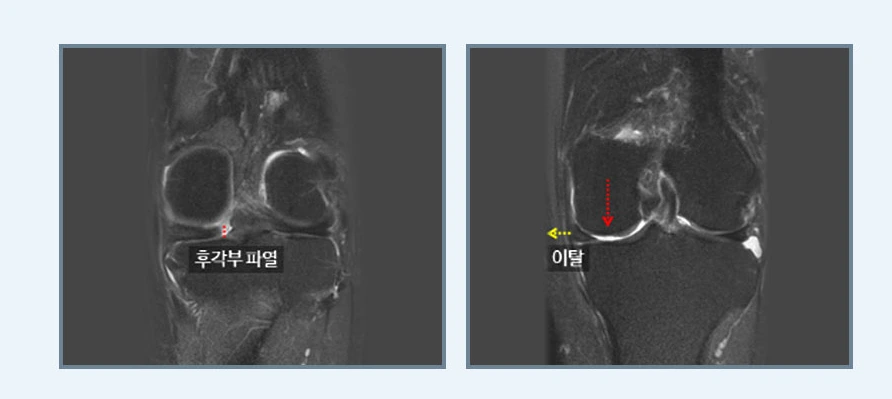

연골판 봉합술

봉합술.PNG

연골판을 봉합해 제 기능을 수행하도록 하는 연골판 봉합술은 크게 후각부 파열과 양동이 손잡이형 파열로 나뉩니다. 연골판의 기능을 보존하기 위해 연골판과 뼈가 부착되어 있는 부분의 가장 후방부인 후각부의 파열을 봉합하는 후각부 파열, 파열부위가 손잡이 젖혀지듯이 움직이기 때문에 관절 사이에 끼어 무릎이 움직이기 힘들어지는 양동이 손잡이형 파열이라고 합니다.

특히 무릎을 구부리는 동작에서 많은 스트레스를 받게 되는 후각부 파열은 생활 습관상 양반다리를 많이 하게 되는 좌식 생활권인 동양권에서 많이 발생합니다. 덧붙여 후각부가 파열되면 연골판의 뿌리가 견고하게 고정되지 않기 때문에 체중이 가해졌을 때 연골판이 고정되지 못하고 밖으로 이탈되는 현상이 발생되어 관절염이 급속하게 진행되기도 한답니다.